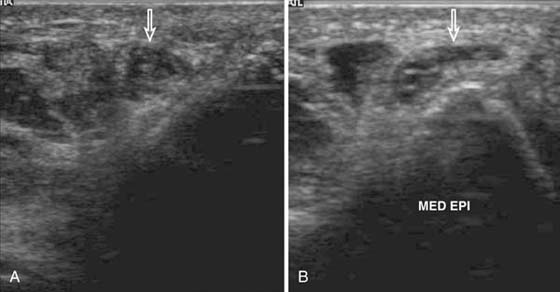

Lateral epicondylitis, or “tennis elbow,” is a chronic tendinopathy of the common extensor origin and is a frequent cause of lateral elbow pain. On MRI, abnormal high signal is seen at the common extensor origin on fluid-sensitive sequences, sometimes with associated partial tears, which are fluid-bright.29 In more severe cases, associated subtendinous bone marrow edema may be present at the lateral epicondyle, but this is not required for radiologic diagnosis. US is a valuable modality for examining the lateral epicondyle.30,31 Sonographic features include common extensor origin thickening, heterogeneous echogenicity, calcific deposits, partial tears, and hypervascularity on Doppler imaging (Fig. 14-12). US may also be used to guide steroid or anesthetic injections and tendon fenestration.32 Medial epicondylitis has similar MRI and US findings at the common flexor origin. Both of these entities may be associated with injury to the adjacent medial and lateral stabilizing structures.33 Evaluation of the other tendons, including the biceps, triceps, and brachialis, is optimized with MRI. US is also useful for directed examination of tendon pathology at the elbow.

images

Figure 14-12 Lateral epicondylitis or common extensor tendinosis with partial tear. Ultrasound image demonstrates thickening of the common extensor origin consistent with tendinosis/epicondylitis with an associated hypoechoic (black) defect within the extensor tendon origin consistent with an interstitial partial tear (arrow). Power Doppler imaging demonstrates hypervascularity (orange areas), often seen with lateral epicondylitis/common extensor tendinosis.

Direct MR arthrography is most useful in detecting suggested injury to the medial and lateral stabilizing ligaments. The medial (ulnar) collateral ligament, for example, is frequently injured in baseball pitchers and can be assessed accurately with MR arthrography34-36 (Fig. 14-13). US is also useful in assessing the elbow ligaments but has an advantage over MRI with its ability to assess ligamentous laxity in real time with dynamic imaging37,38 (Fig. 14-14). For example, during valgus stress for assessment of the medial collateral ligament, a difference in 2 mm between sides is diagnostic of abnormal ligamentous laxity.

Figure 14-14 Ulnar collateral ligament (UCL) instability. A, Ultrasound at rest. Medial elbow joint demonstrates minimal gapping between the trochlea of humerus and ulna measured by crosshairs. B, When manual valgus stress is applied this gap increases significantly (difference of 3.9 mm) consistent with UCL instability. The difference between rest and stress measurement should be less than 2 mm. Multiple measurements (e.g., 3) should be taken and the average calculated. It is also useful to compare with the asymptomatic elbow.